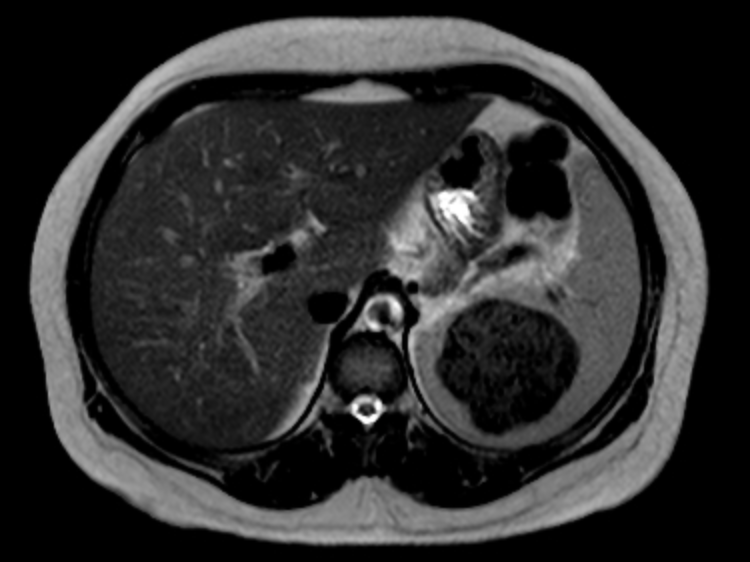

There is inversion of some abdominal structures (liver, spleen and stomach) with thoracic structures in normal position. Multiple splenules are seen on right hypochondrium. The study protocol was made for chest CT.

Case Discussion

Situs inversus partialis refers to any kind of incomplete organs inversion, like in this case. Malformations associations are more frequent in situs inversus partialis than in situs inversus totalis.